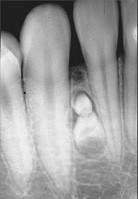

问题 组图为牙瘤的外观及X?线表现,有关此病的描述错误的是()

选项 A.多见青年人 B.生长缓慢,早期无自觉症状 C.由牙胚组织异常发育增生而形成 D.X?线可见类似发育不全牙的影像 E.绝大多数为恶性

答案 E